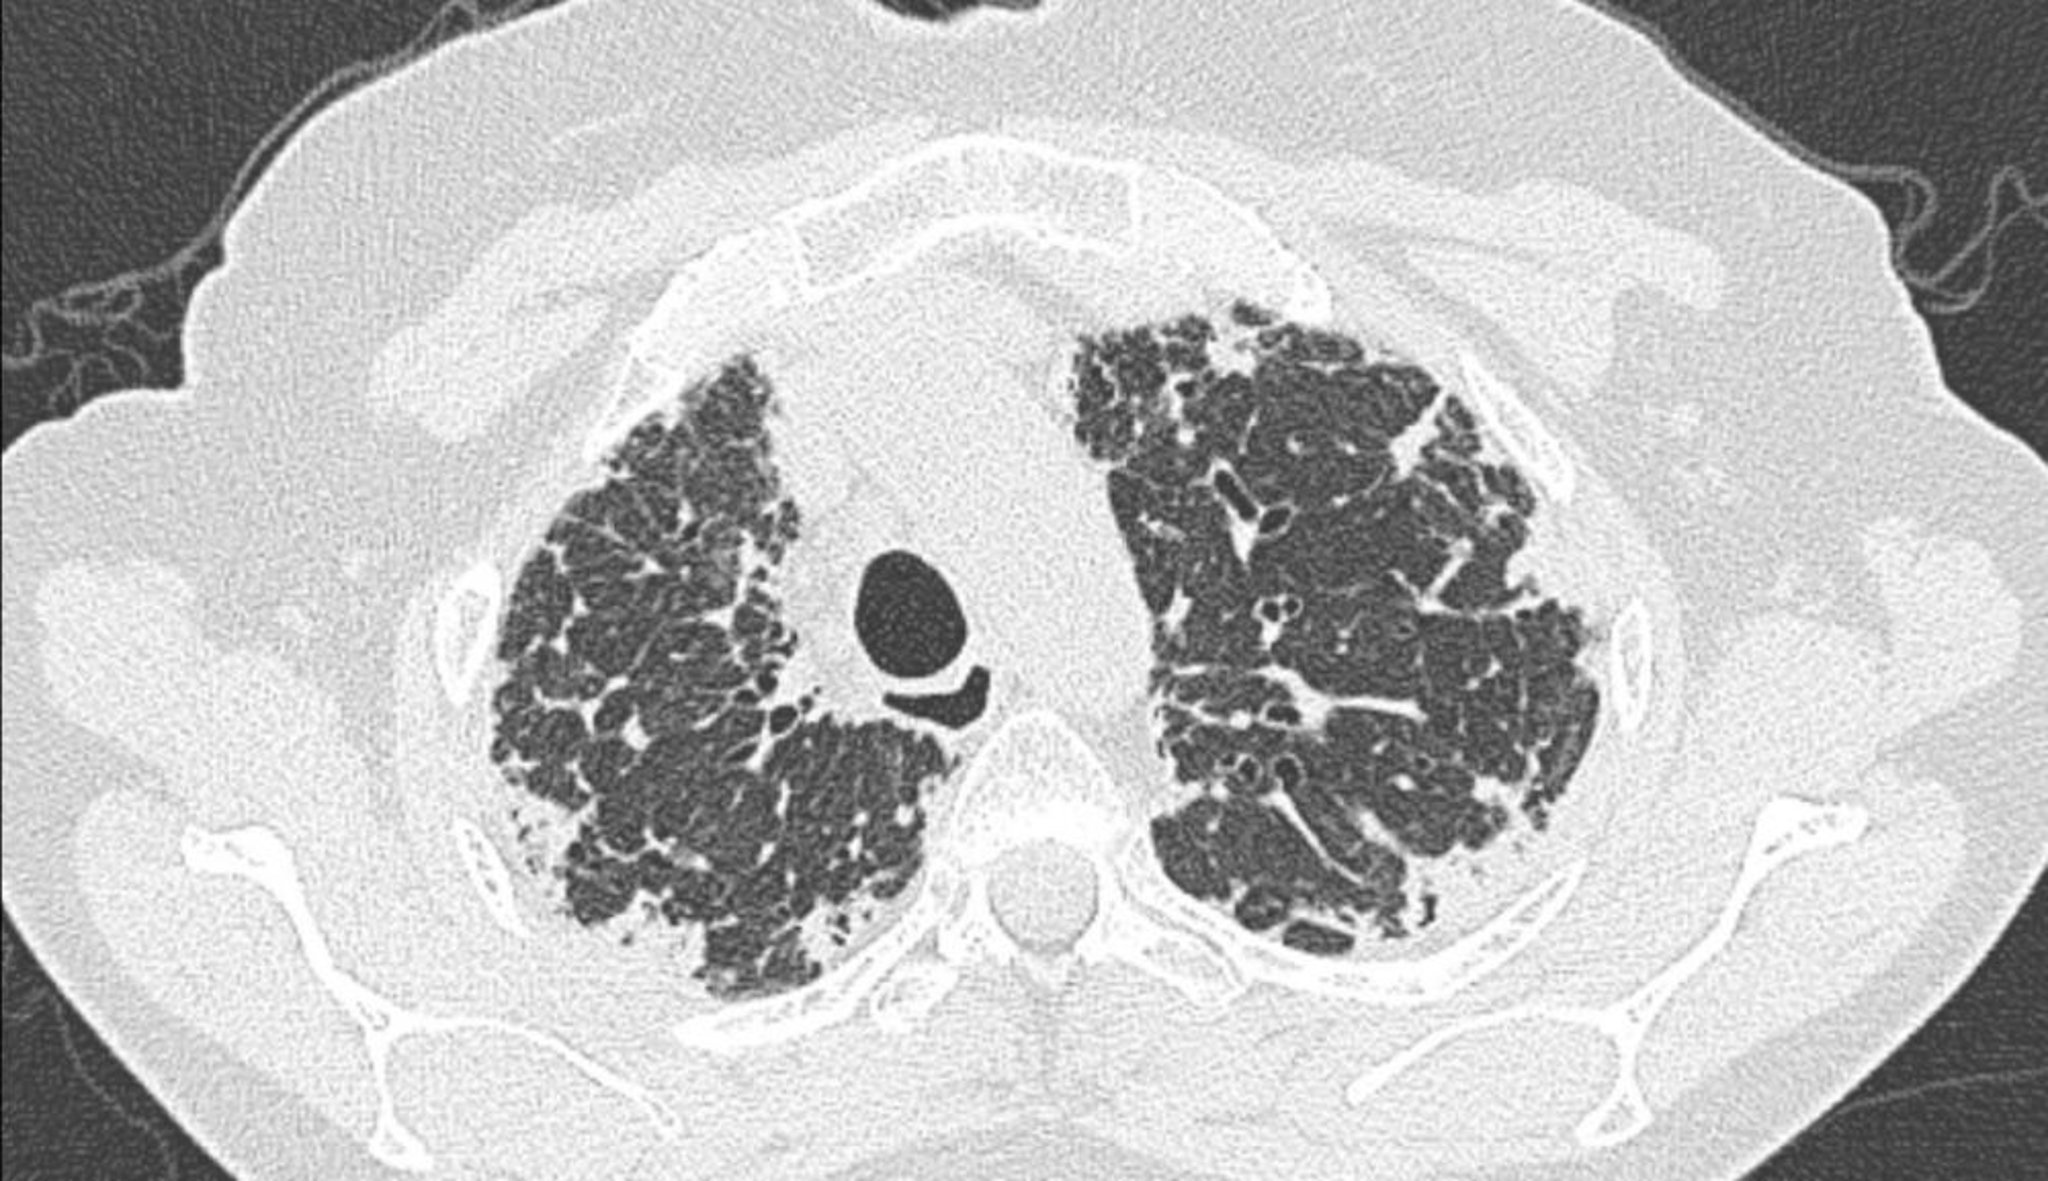

Идиопатический плевропаренхиматозный фиброэластоз (КТ-сканирование)

КТ-скан грудной клетки показывает плевральное и субплевральное утолщение.

Image courtesy of Joyce S. Lee, MD, MAS.